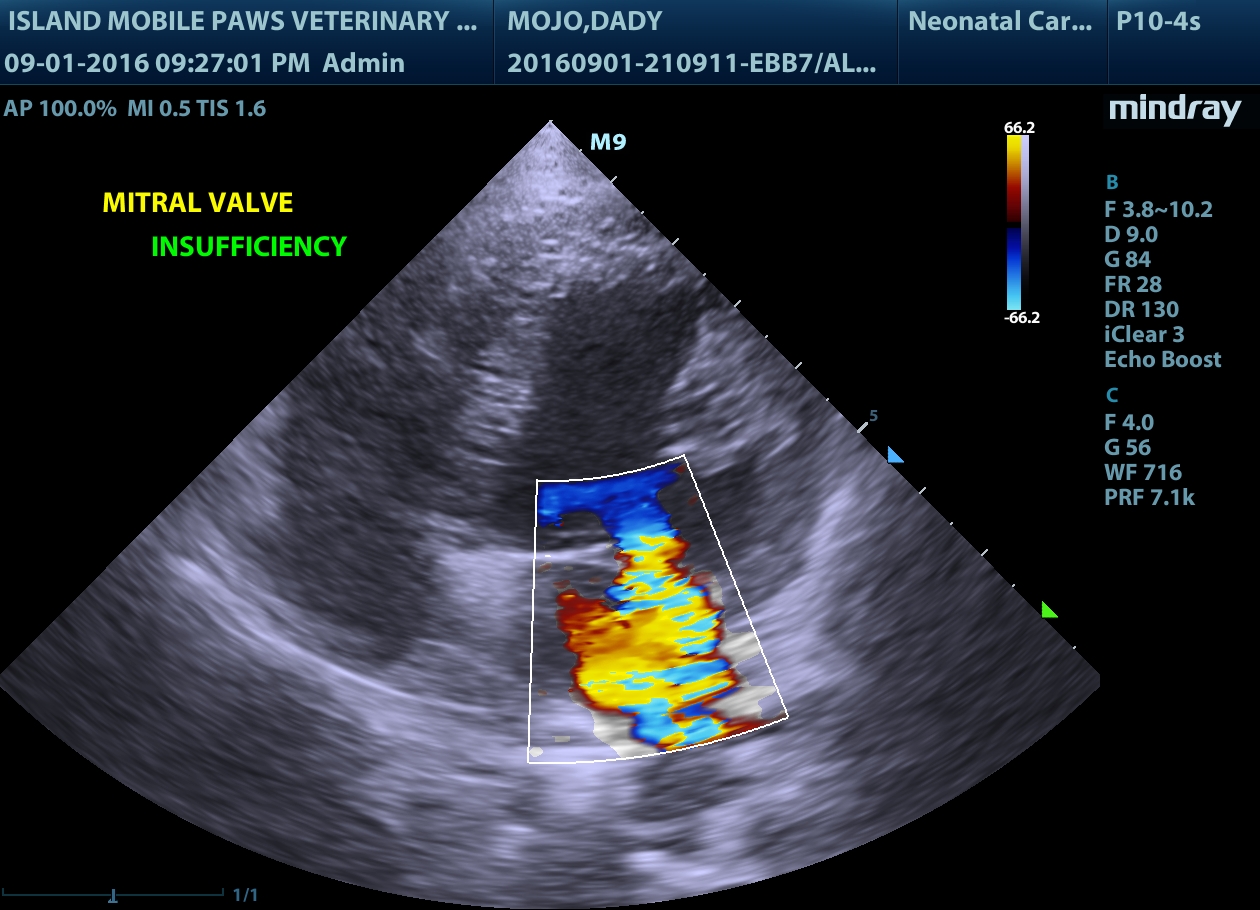

If more information is needed to guide treatment, a cardiac ultrasound is used to obtain video clips and pictures of the heart chambers as they are contracting. This allows us to see which parts of the heart are too big, which portions of the heart muscle are not functioning well, and where there is abnormal blood flow or pressure.